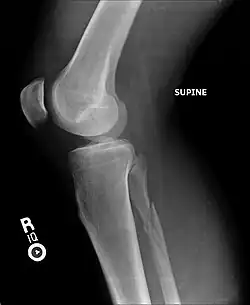

| Radiograph showing a Maisonneuve fracture of the proximal fibula | |

Ankle radiographs are used to detect widening of the tibiofibular syndesmosis or medial clear space. The medial clear space is the area between the talus of the ankle and the medial malleolus. Damage to the deltoid ligament and syndesmotic ligaments result in mortise instability, causing the talus to laterally shift and widen the medial clear space.[4][12] A clinical study, conducted in 2006 and published in the Journal of Bone and Joint Surgery, found that the medial clear space size of a normal ankle and an injured ankle measured at 4 millimetres and 5.4 millimetres in length respectively.[11] To confirm diagnosis, full-leg radiographs are used to inspect for fractures of the proximal fibula and widening of the interosseous clear space (or tibiofibular clear space). The interosseous clear space is the area between the medial side of the fibula and lateral side of the tibia. A peer-reviewed study, published in Injury in 2004, found that an interosseous clear space greater than 10 millimetres indicates diastasis of the syndesmotic ligaments.[4]

If necessary, Computed Tomography (CT) or Magnetic Resonance Imaging (MRI) may also be used to clarify diagnosis. MRI scans can check for interosseous membrane or tibial tubercle damage if high instability of the ankle is diagnosed.[8][11] Arthroscopy may be used to diagnose a syndesmotic lesion but is often not recommended due to operative difficulty.[13] Stress radiographs of the ankle are used to assess the integrity of the deltoid ligament and tibiofibular syndesmosis.[9][13] The size of the medial clear space can also be measured using stress radiography.[11]

X-ray, CT, or MRI scans can be used to diagnose the extent of the Maisonneuve fracture's damage and determine whether it is a simple or comminution fracture.[8] During diagnosis, a supination-external rotation pattern of injury may also be concluded if there is an isolated fracture of the posterior tubercle of the tibia.[9]